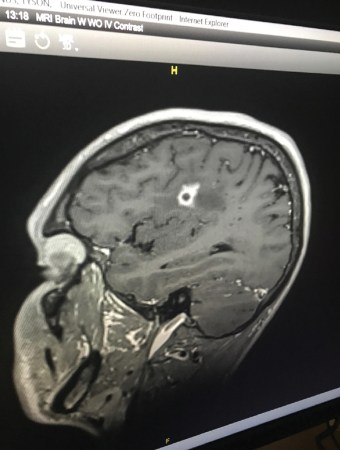

About a month after returning to Rhode Island, Bottenus started having headaches. He couldn’t control his mouth properly — his speech was off, and he was drooling. Eventually his doctor ordered an MRI, which revealed a lesion in his brain. “My first thought was, I must have some sort of cancer,” he says. “I’m only 31…. I’m way too young for this.”

It wasn’t cancer. Nor was it any of the infections proposed as doctors searched for a diagnosis. Two brain biopsies didn’t provide enough tissue to identify the problem.

Finally, a third brain biopsy, taking a slightly larger amount of tissue, yielded a diagnosis: Bottenus had a fungus growing in his brain. It was a black mold called Cladophialophora bantiana that can breach the blood-brain barrier. The best medical guess is that Bottenus was exposed in Costa Rica — probably from the dusty air he inhaled, or maybe from the debris-laden wound on his elbow.

Into this uncertain medical terrain landed Bottenus, a previously healthy young man who acquired an exceedingly rare fungal infection in his brain.

Bottenus has been treated with antifungal drugs and steroids. It’s been a “vicious cycle,” says Robbie Goldstein, an infectious disease physician at Massachusetts General Hospital who has been part of Bottenus’ team of doctors. The steroids reduce the inflammation from the infection, which puts dangerous pressure on Bottenus’ brain. But the steroids also suppress his immune system, impairing his ability to clear the fungus. When doctors have tried to taper the steroids, the inflammation in Bottenus’ brain has gotten worse.